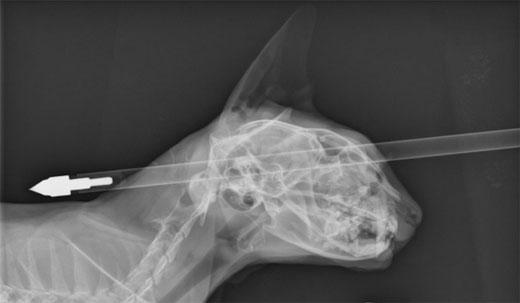

25일(현지시간) 뉴질랜드 매체 스타프 등 현지 언론에 따르면 최근 뉴질랜드 와이누이오마타에서 한 집 고양이가 자신의 머리에 석궁 화살이 꽂히는 끔찍한 사고를 당했다.

1주 전 무무(Moo Moo)라는 6살 고양이는 두개골에 화살이 꽂히는 사고를 당했다.

고양이 주인 도나 페라리는 다친 무무를 살리기 위해 인근 대학동물병원으로 급히 데리고 갔고 무무는 다행히 응급 수술을 받을 수 있었다.

주치의 조나단 브레이 박사는 “그는 엄청나게 운 좋은 고양이다”면서 “상처는 코와 눈구멍에 약간의 손상만 입은 정도였다”고 설명했다.